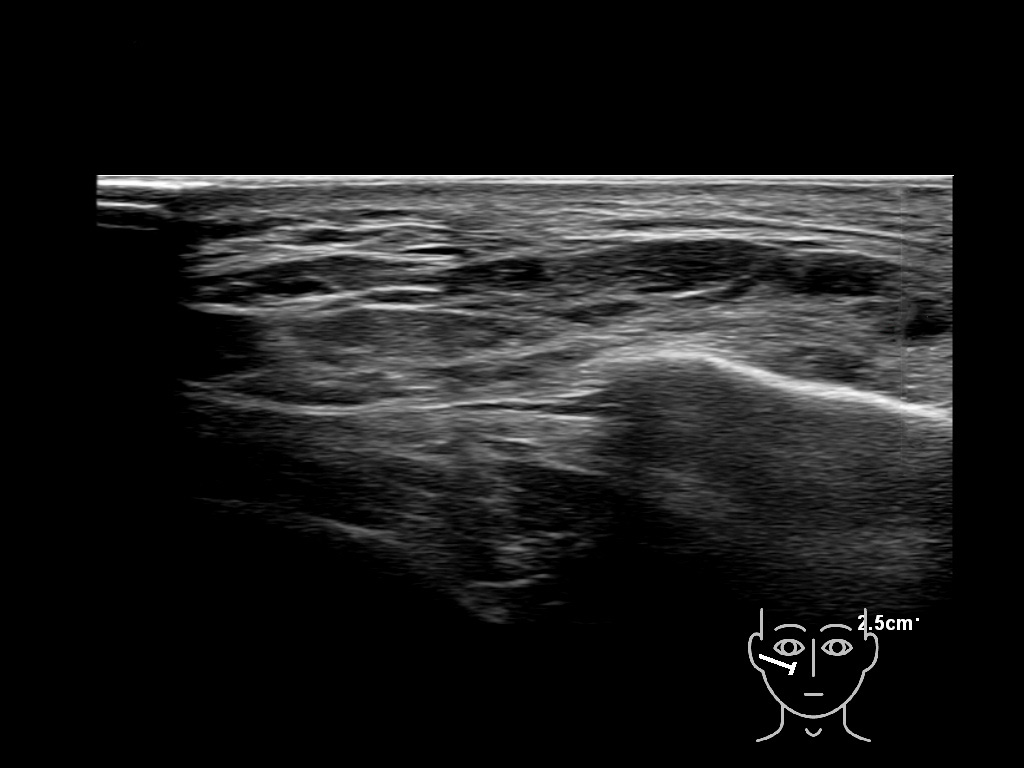

Fascia

Filler deposits may end up unintentionally in the SMAS or fascial layers of the skin. Very often this will not lead to adverse events, however, adverse events ( nodules, migration / redistribution impaired muscle movement and smiling and malar edema) are are often related to filler ending up in the SMAS or fascia.

Study the first image to recognize the different layers. If you are sure about the layers, swipe to the second image to view the answer (if applicable).